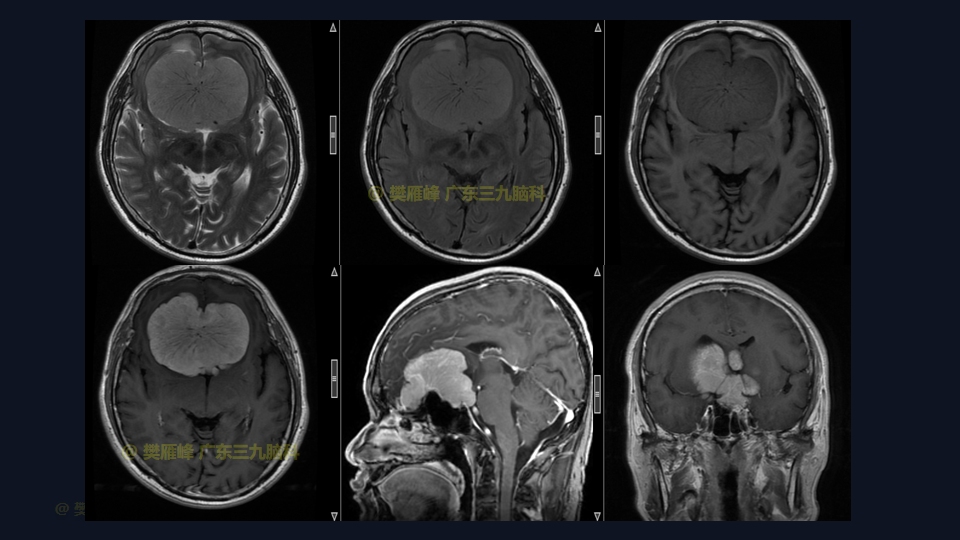

在这个二维手术视频中,展示了一种经前纵裂额底入路切除巨大嗅沟脑膜瘤的方法。患者是一名52岁的男性,有双眼视物模糊3月、无步态不平衡病史,神经影像学显示前颅窝、双侧鞍旁、桥前池示一巨大团块状等T1长T2,FLAIR序列高信号,明显强化,其内示多发流空信号影,邻近双侧颈内动脉及双侧大脑前动脉被包绕,大小约77×62×51mm的嗅沟脑膜瘤。术中实现肿瘤全切除。术后3月双侧嗅觉基本同术前,双侧视力较术前好转,神经影像学显示肿瘤全切。我们展示了安全的颅神经和肿瘤切除术的细微差别和技术要点,包括:采用降低硬膜开口的颅底法,保留额叶静脉,防止静脉损伤。诊断时,尽管患者嗅觉常常缺失,但仍有至少保留一根嗅觉通路。通过精准的解剖重视A2段的保护。最后,需要多层重建颅底。